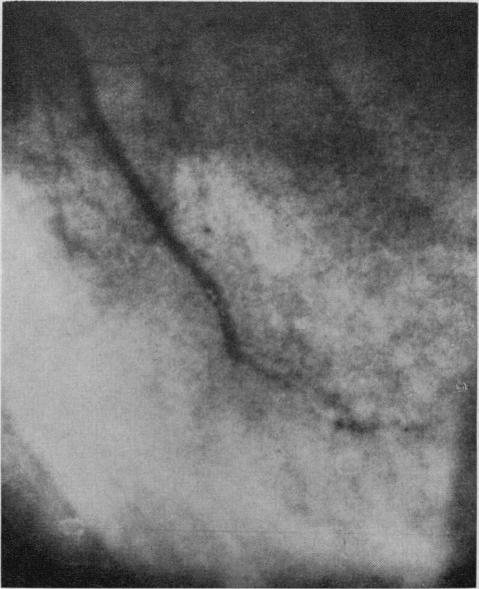

Atherosclerosis obstructs the main stems of coronary arteries, restricting the coronary artery inflow tract. Nature develops intramyocardial collaterals but fails to form extracoronary collateral channels. It is only through surgical measures that extracoronary collateral channels may be formed, for example, by internal mammary artery implantation and omental graft without pedicle operations. Preoperative assessment, with particular reference to anginal pain, disease activity, indications for and contra-indications to surgery, is outlined. The importance of cine coronary arteriography is stressed. The results of internal mammary artery implantation with or without omental graft in patients followed up for two to 14 years are presented. Operative mortality in 103 consecutive patients was 2.9%. There was marked improvement in over 70% of 115 patients reviewed. Post-operative examination of 29 implanted internal mammary arteries showed that 76% were open when examined up to 10 years postoperatively; many of these were studied by cineangiography.